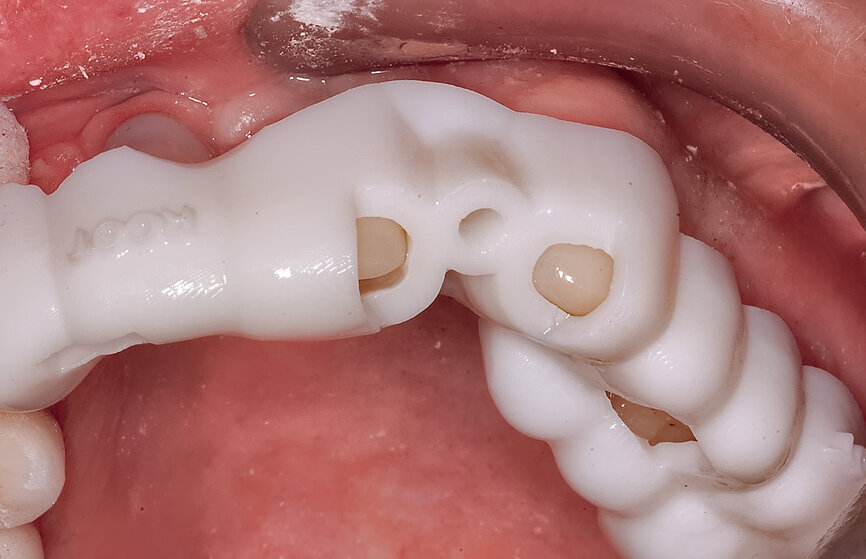

Fig. 11: The stackable tooth-borne guide and the three other separate components.

The first concept described the use of two separate templates, one for separating the root at the apex and the second for drilling through the tooth and placing the implant. Continuing the evolution, we present a second option, which does not require the removal of the base template, but has inserts to allow for the different drills and angulation required for the PET technique: the stackable tooth-borne guide. The new technique has four separate components: (1) a base template (stackable tooth-borne guide); (2) a pilot drill guide for the root ape (APEX STACK); (3) a crescent-shaped guide for shaping root fragments (PET Shaper STACK); and (4) a guide for osteotomy drilling and placing the implant through the guide (Surgical Guide STACK; Fig. 11).